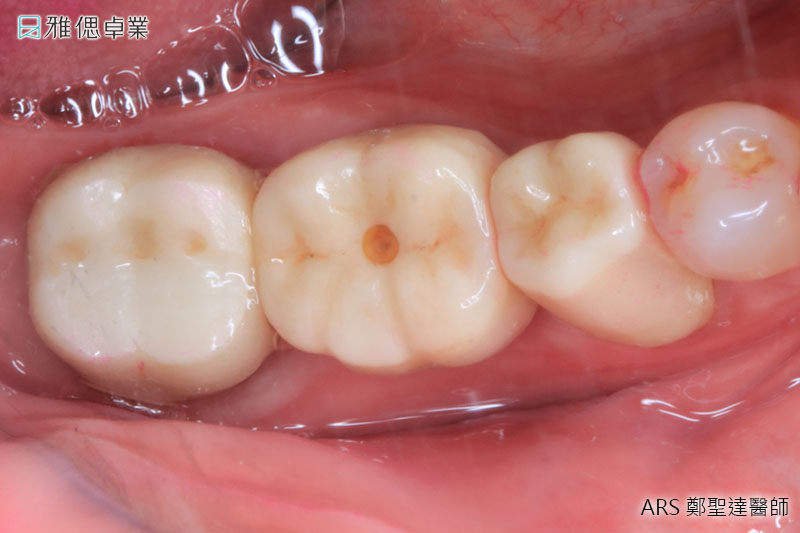

在植牙前擬定治療計畫時需考慮

牙齒基本治療

包括齲齒填補、根管治療或假牙重建等。

牙周病治療

包括基本牙結石去除、噴砂將牙齒表面沉積物去除、水雷射牙周治療或手術牙周治療。